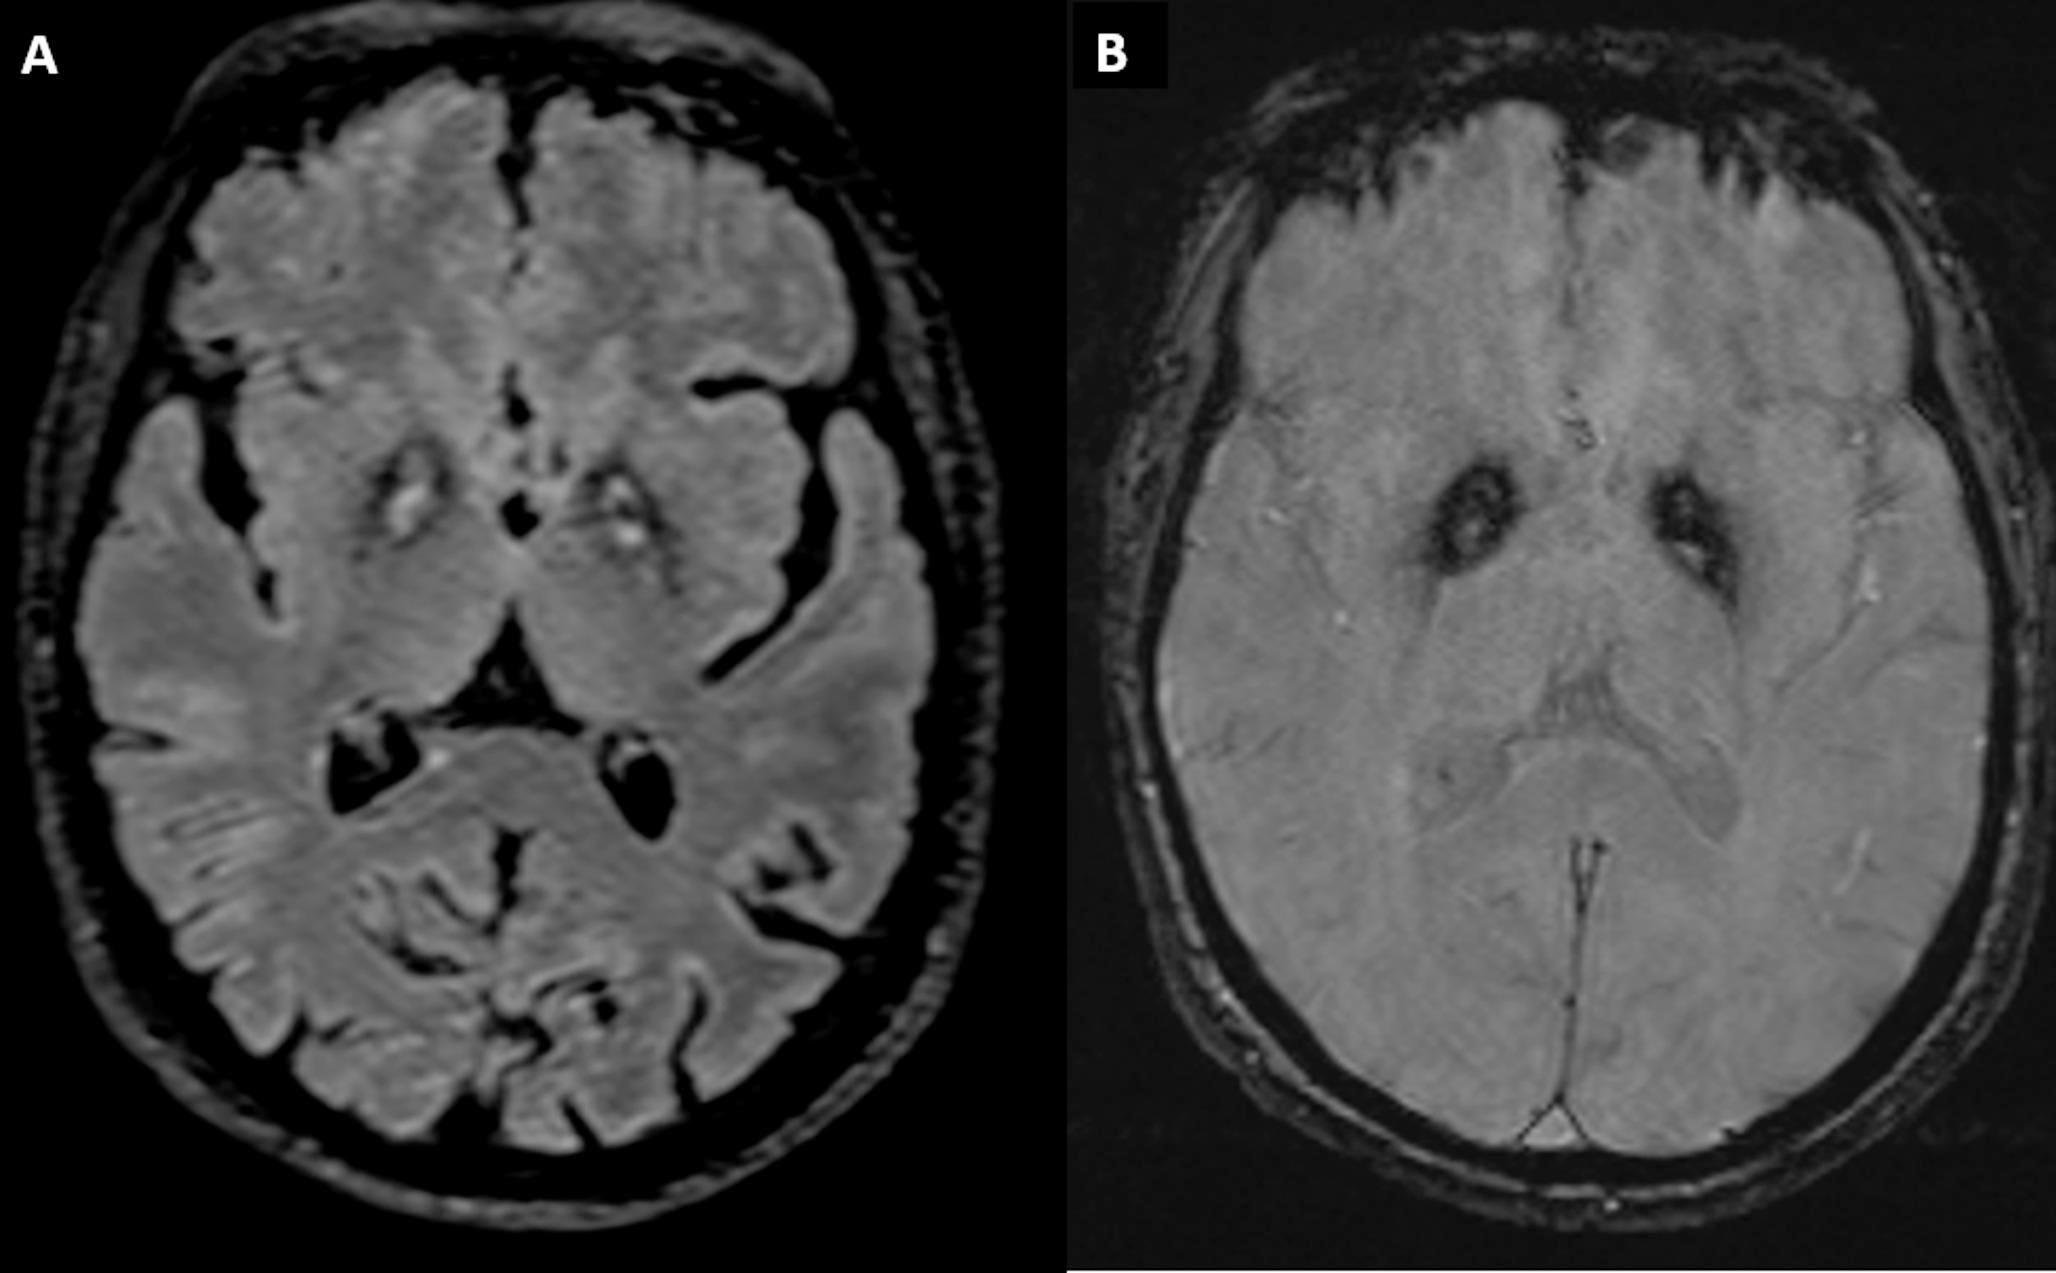

Brain magnetic resonance imaging (MRI) showed an “eye of the tiger” sign, defined by a bilateral central region with hyperintense signal surrounded by hypointensity in the globus pallidus on T2-weighted sequences (Fig. 1) [1]. There was no evidence of cerebellar or cortical atrophy. Fluorodeoxyglucose positron emission tomography (FDG-PET) and I-123 ioflupane single-photon emission computed tomography (DATscan) were normal, in accordance with previous cases reported (Fig. 2) [2, 3].

Fig. 1

Brain MRI Imaging. (A) Axial-slice of T2-FLAIR weighted sequences with the classical “Eye of the tiger sign” defined by a bilateral central region with hyperintense signal surrounded by hypointensity in the globus pallidus. (B) Axial slice of Susceptibility Weighted Imaging sequences showing susceptibility artifact (low signal) in corresponding areas from iron deposition

The MRI characteristic pattern with the “eye of the tiger” sign in the globus pallidus is pathognomonic of PKAN disease [1].